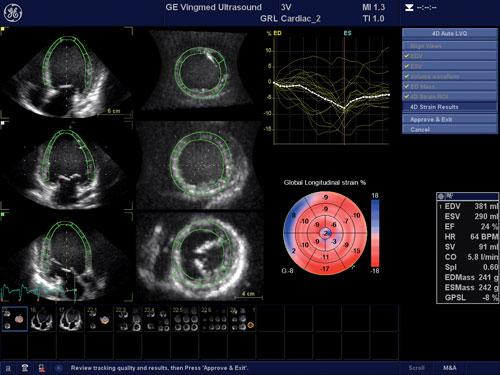

A recent echocardiographic study4 of 1,820 adult survivors of childhood cancer using 3-D LV ejection fraction (LVEF) and strain imaging found abnormal global longitudinal strain and diastolic function may better identify subsets of survivors at higher risk for poor clinical cardiac outcomes who may benefit from early medical intervention. Only 5.8 percent of survivors had abnormal 3-D LVEFs of less than 50 percent. However, 32.1 percent of survivors with normal 3-D LVEFs had evidence of cardiac dysfunction by global longitudinal strain (28 percent). Abnormal global longitudinal strain was associated with patients who received chest-directed radiotherapy and an anthracycline dose of more than 300 mg/m2.